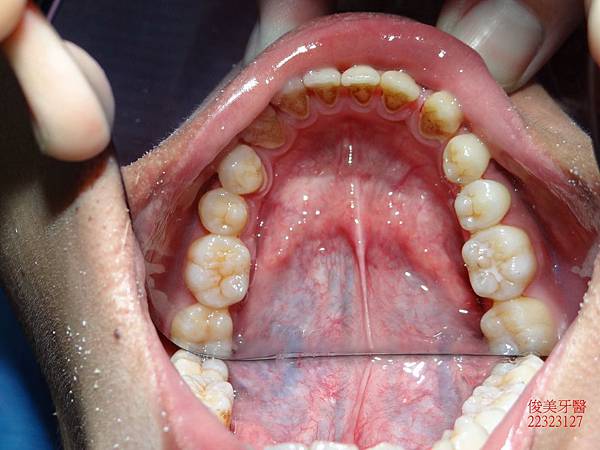

原始狀況~~

上顎牙弓形狀